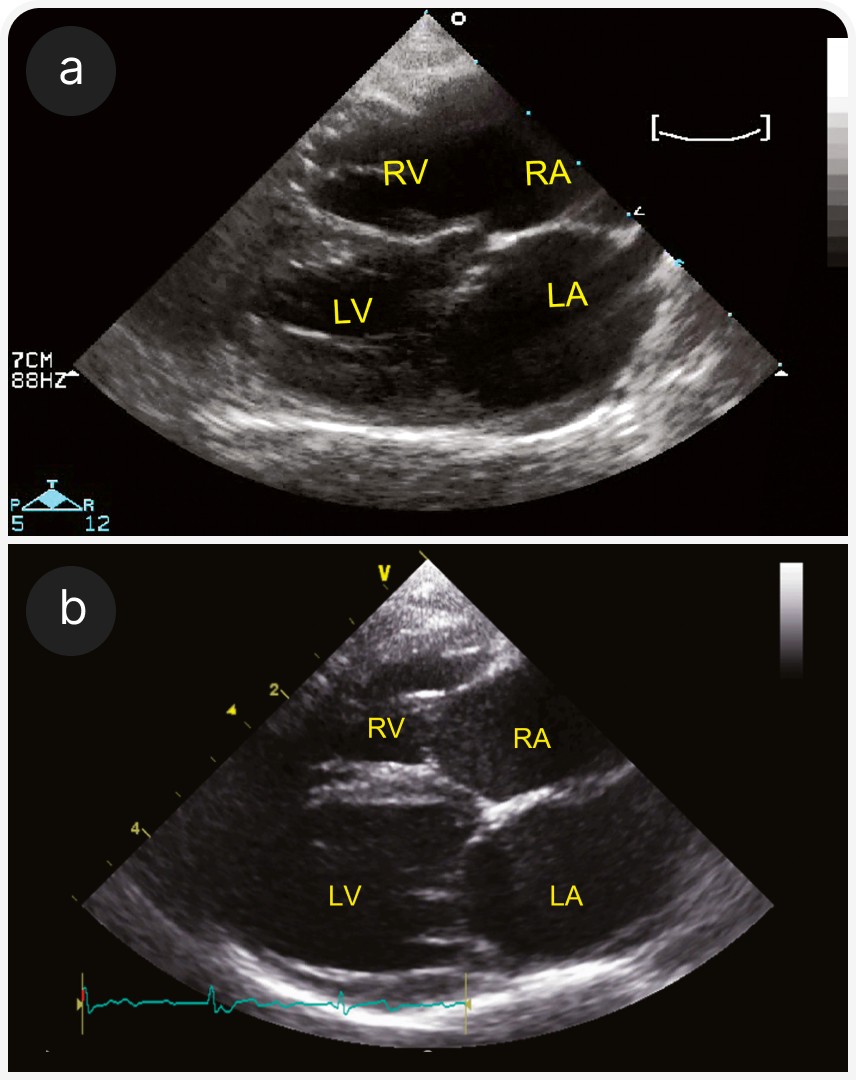

1. Терминальная стадия гипертрофической кардиомиопатии. На сегодняшний день ГКМП — наиболее распространенный тип кардиомиопатии, но на конечных стадиях она может проявляться другими фенотипами. Этот термин используют, если ГКМП отмечена в анамнезе, даже если при обследовании не выявлена сегментарная или генерализованная гипертрофия левого желудочка или выявлена очень легкая гипертрофия. Левый желудочек может быть гипокинетичным или расширенным (Рисунок 2), может быть виден инфаркт миокарда (Рисунок 3).

2. Рестриктивная кардиомиопатия (РКМП). РКМП без гипертрофии и расширения полостей или сопровождающаяся дилатацией левого или обоих предсердий (Рисунок 4) с диастолической дисфункцией, рестриктивным характером наполнения сердца, характеризуется более чем в два раза более высокой скоростью трансмитрального потока Е по сравнению со скоростью волны А. Обратите внимание, что эта форма диастолической дисфункции неспецифична для РКМП, но может возникать при любой кардиомиопатии. Подразделяется на миокардиальную форму (22), без особенностей эндокарда (Рисунок 4), и эндомиокардиальную форму (23, 24), при которой эндокард может быть неравномерно утолщенным и эхогенным, с рубцовыми мостиками, которые могут вызывать внутрижелудочковую обструкцию (Рисунок 5). Предрасположенность описана для кошек сиамской или ориентальной пород.